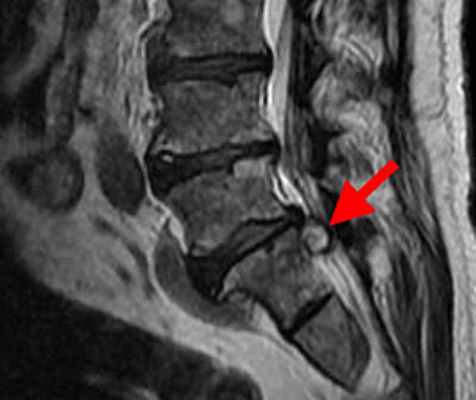

б) Визуализация экстрадуральной арахноидальной кисте крестца:

• Равномерное правильной формы расширение спинномозгового канала крестца:

о Раздвигает, однако не нарушает целостность костных стенок крестца

о Отсутствует расширение или ремоделирование крестцовых отверстий

• Характерно наличие вдавление в области задней стенки крестца

• Отсутствие контрастного усиления стенки кисты

(Слева) На этой схеме пояснично-крестцового отдела позвоночника показана экстрадуральная киста, расположенная в спинномозговом канале ниже окончания дурального мешка на уровне S2. Обратите внимание на ремоделирование костных стенок спинномозгового канала на уровне кисты.

(Справа) Т1-ВИ, сагиттальная проекция: в спинномозговом канале крестца определяется небольшая экстрадуральная киста, интенсивность сигнала которой соответствует жидкости. Такая локализация типична для скрытого крестцового менингоцеле, которое в настоящее время носит название экстрадуральной арахноидальной кисты. В полости кисты не определяется ни солидного, ни жирового компонентов. (Слева) На сагиттальном Т2-ВИ в каудальной части спинномозгового канала визуализируется небольшая экстрадуральная арахноидальная киста крестца. Конус спинного мозга оканчивается на нормальном уровне. Обратите внимание на то, что интенсивность сигнала от кисты несколько выше, чем от СМЖ в дуральном мешке, что отражает повышенное содержание в полости кисты белка.

(Справа) Аксиальное Т1-ВИ крестца на уровне арахноидальной кисты подтверждает некоторое ремоделирование костных стенок каудальной части спинномозгового канала, вызванное объемным воздействием кисты.